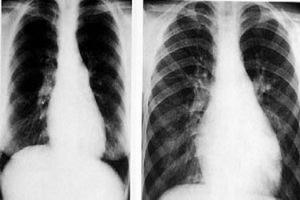

對比圖片(1)高齡:肺動脈栓塞並非原發性疾病,它是許多疾病的一種嚴重合併症。在老年人中,由於各種疾病如充血性心力衰竭、動脈粥樣硬化性心臟病、惡性腫瘤、腦血管疾病、外科大手術後、長期臥床和下肢活動受限是血栓形成的高危因素。50~65歲者肺動脈栓塞的發病率最高,肺動脈栓塞是70歲以上老年人的常見死亡原因,因此對大面積肺段、肺葉、較小或反覆出現的肺動脈栓塞做出及時診斷,對降低老年患者的病死率有積極作用。

2.X線檢查肺部可出現肺下葉卵圓形或三角形浸潤陰影,其底部連及胸膜,亦可有胸腔積液陰影。一側肺門血管陰影加深及同側膈肌上升。兩側肺動脈栓塞時,其浸潤陰影類似支氣管肺炎。重症患者可出現肺動脈段明顯突出,心影增大及奇靜脈與上腔靜脈陰影增寬。如做選擇性肺動脈造影,則可準確地了解栓塞所在部位和範圍,為手術治療提供依據。